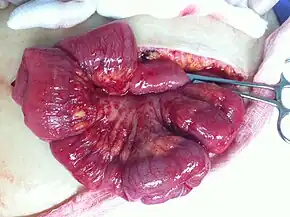

A pathological specimen of ovarian carcinoma

Epithelial ovarian cancer typically presents at an advanced stage and is derived from the malignant transformation of the epithelium of the ovarian surface, peritoneum, or fallopian tube.[65] It is the most common cause of gynecologic cancer death.[65] There are various types of epithelial ovarian cancer, including serous tumor, endometrioid tumor, clear-cell tumor, mucinous tumor, and undifferentiated or unclassified tumors.[66] Annually worldwide, 230,000 women will be diagnosed and 150,000 will die.[67] It has a 46% 5 year survival rate after diagnosis because of the advanced stage of the disease at the time of diagnosis.[67] Typically, around 75% of patients are diagnosed as having an advanced stage of the disease because of the asymptomatic nature of its presentation.[67] There is a genomic predisposition to epithelial ovarian cancer and the BRCA1 and BRCA2 genes have been found to be the causative genes in 65-75% of hereditary epithelial ovarian cancer.[67]